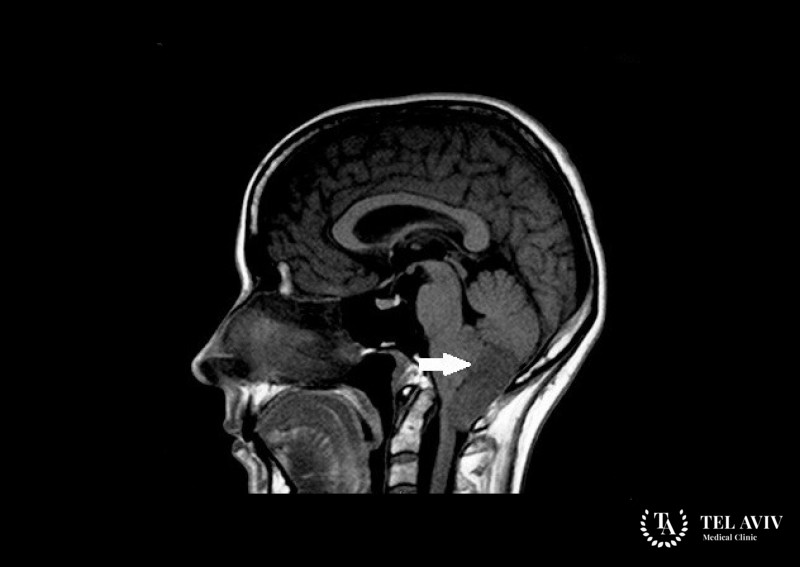

Гемангиобластома головного мозга – это развивающаяся из кровеносных сосудов доброкачественная опухоль, которая зачастую локализуется в мозжечке. К основным факторам, повышающим […]